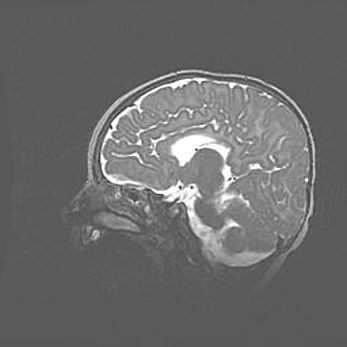

Аномалия Денди-Уокера. Признаки гипоплазии мозолистого тела.

Возраст: 5 месяцев 3 дня

Вес: 5550 г

Пол: мужской

Окружность головы: 39 см

Срок гестации: 40 недель

Аномалия Денди-Уокера – это порок развития головного мозга, для которого характерна триада симптомов: гипотрофия или аплазия червя мозжечка и/или полушарий мозжечка, расширение четвёртого желудочка с формированием ликворной кисты задней черепной ямки, гипертензионная гидроцефалия различной степени.

Гипоплазия мозолистого тела относится к дефектам внутриутробного этапа развития мозговой ткани, возникающим в процессе закладки структур головного мозга, что происходит на начальных этапах развития эмбриона.